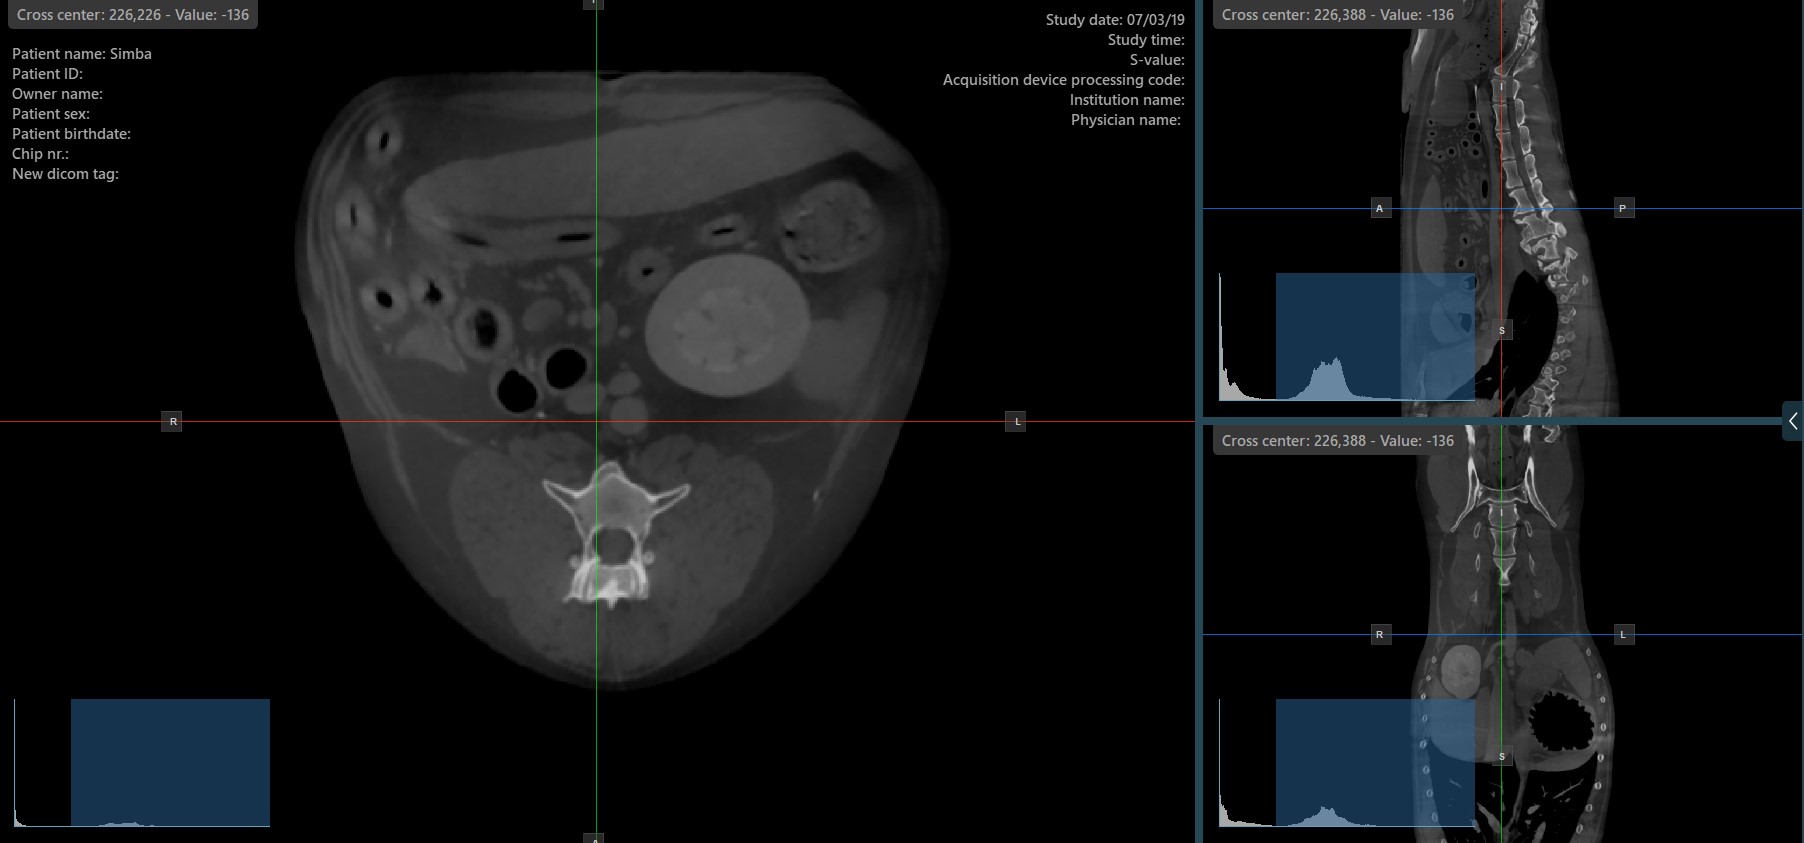

Die Slicer in der MPR-Ansicht zeigen die Schnittpunkte und die Orientierung der drei Bild-Ebenen, die in den aktiven Ansichtsbereichen angezeigt werden. Benutzer können die Slicer ändern und die Querschnittsposition der Schichten basierend auf den 3D-volumetrischen Daten anpassen.

Jeder Slicer ist durch seine spezifische Farbe gekennzeichnet, die die jeweilige Bildebene darstellt:

Der blaue Slicer markiert die axiale Ebene des Objekts (senkrecht zum Boden).

Der rote Slicer markiert die koronale Ebene (parallel zum Boden).

Der grüne Slicer markiert die sagittale Ebene (senkrecht zum Körper).

Das Ändern der Rotation eines Slicers verändert die Orientierung der entsprechenden Bildebenen. Einzelne Slicer können mit dem Werkzeug Select Item (Default) ausgewählt werden, das standardmäßig der rechten Maustaste zugewiesen ist.

Sobald der bestimmte Slicer ausgewählt ist, ziehen Sie ihn in die gewünschte Richtung, um ihn zu drehen. Die Orientierung der entsprechenden Bildebene ändert sich entsprechend.